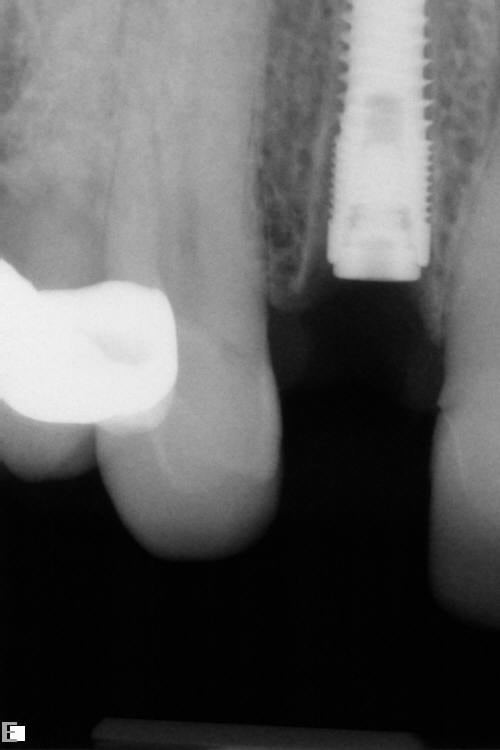

In February 2012 the patient enrolled in the multicenter study, and a 5.5-mm x 11.5-mm implant (Genesis) was placed (Figure 42). Minor contour bone grafting of the site was also performed using autogenous bone directly against the buccal cortex and layered thereafter with a corticocancellous allograft (Puros) along the lateral aspect of the implant. This was done to increase the peri-implant bone and mucosal thickness (existing bone thickness was <1 mm on the buccal aspect) in an effort to improve parameters that would reduce the incidence of recession over the long term.

The 5.5-mm implant platform was used to accommodate the high occlusal load typically associated with the molar area and to optimize the esthetic emergence profile of the final restoration, neither of which would have been feasible with a narrower implant, even in the presence of more robust socket augmentation. A healing abutment was placed (Figure 43).

A high implant stability quotient (Osstell® ISQ = 80) (Osstell, www.osstell.com) and insertion torque values >50 Ncm allowed the prosthetic phase to begin in April 2012 (Visit 3). Figure 44 shows the periapical radiograph at Visit 3; Figure 45 shows good healing and tissue tone at this visit as well.

Figure 50 shows the final periapical view of the osseointegrated implant, abutment, and final screw-retained PFM crown at the 18-month follow-up (Visit 7). Bone loss of 1 mm to 2 mm is radiographically apparent around the implant in this view, as compared to 2 months post-implant placement (Figure 44). However, this is likely of little or no clinical significance, because no PD recorded at 18 months exceeded 3 mm (Table 6). The process by which this bone loss probably occurred is discussed below.